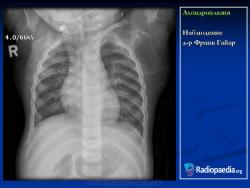

Наблюдение д-ра Франк Гайар

Ахондроплазия - одна из немногих скелетных дисплазий, совместимая с жизнью и практически не требующая социальной адаптации. Прогноз для интеллектуального развития детей хороший. Однако в тех случаях, когда это заболевание возникает как гомозиготная форма, оно становится летальным и проявляет себя выраженным укорочением конечностей и узкой грудной клеткой. У таких пациентов плохой постнатальный прогноз связан с гипоплазией легких, которая развивается вторично в связи с нарушением развития грудной клетки.

Ахондроплазия